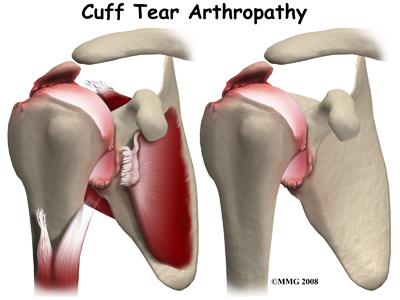

A normal functioning rotator cuff helps to keep the shoulder stable so that it can move well, and also helps to create part of the joint capsule, which holds the joint fluid that lubricates the joint. Over time, a shoulder without an intact rotator cuff becomes arthritic; the shoulder joint wears out due to the abnormal motion in the joint, the instability, and the decreased joint fluid lubrication. This type of wear and tear arthritis in the shoulder is called (rotator) cuff tear arthropathy.

Cuff tear arthropathy is difficult to treat. The shoulder is weak and painful. Patients may not be able to raise the arm above shoulder level. Patients with this type of arthritis would seem to be good candidates for a shoulder replacement, but replacing the shoulder in the traditional fashion has not been successful.

Cuff tear arthropathy is difficult to treat. The shoulder is weak and painful. Patients may not be able to raise the arm above shoulder level. Patients with this type of arthritis would seem to be good candidates for a shoulder replacement, but replacing the shoulder in the traditional fashion has not been successful.